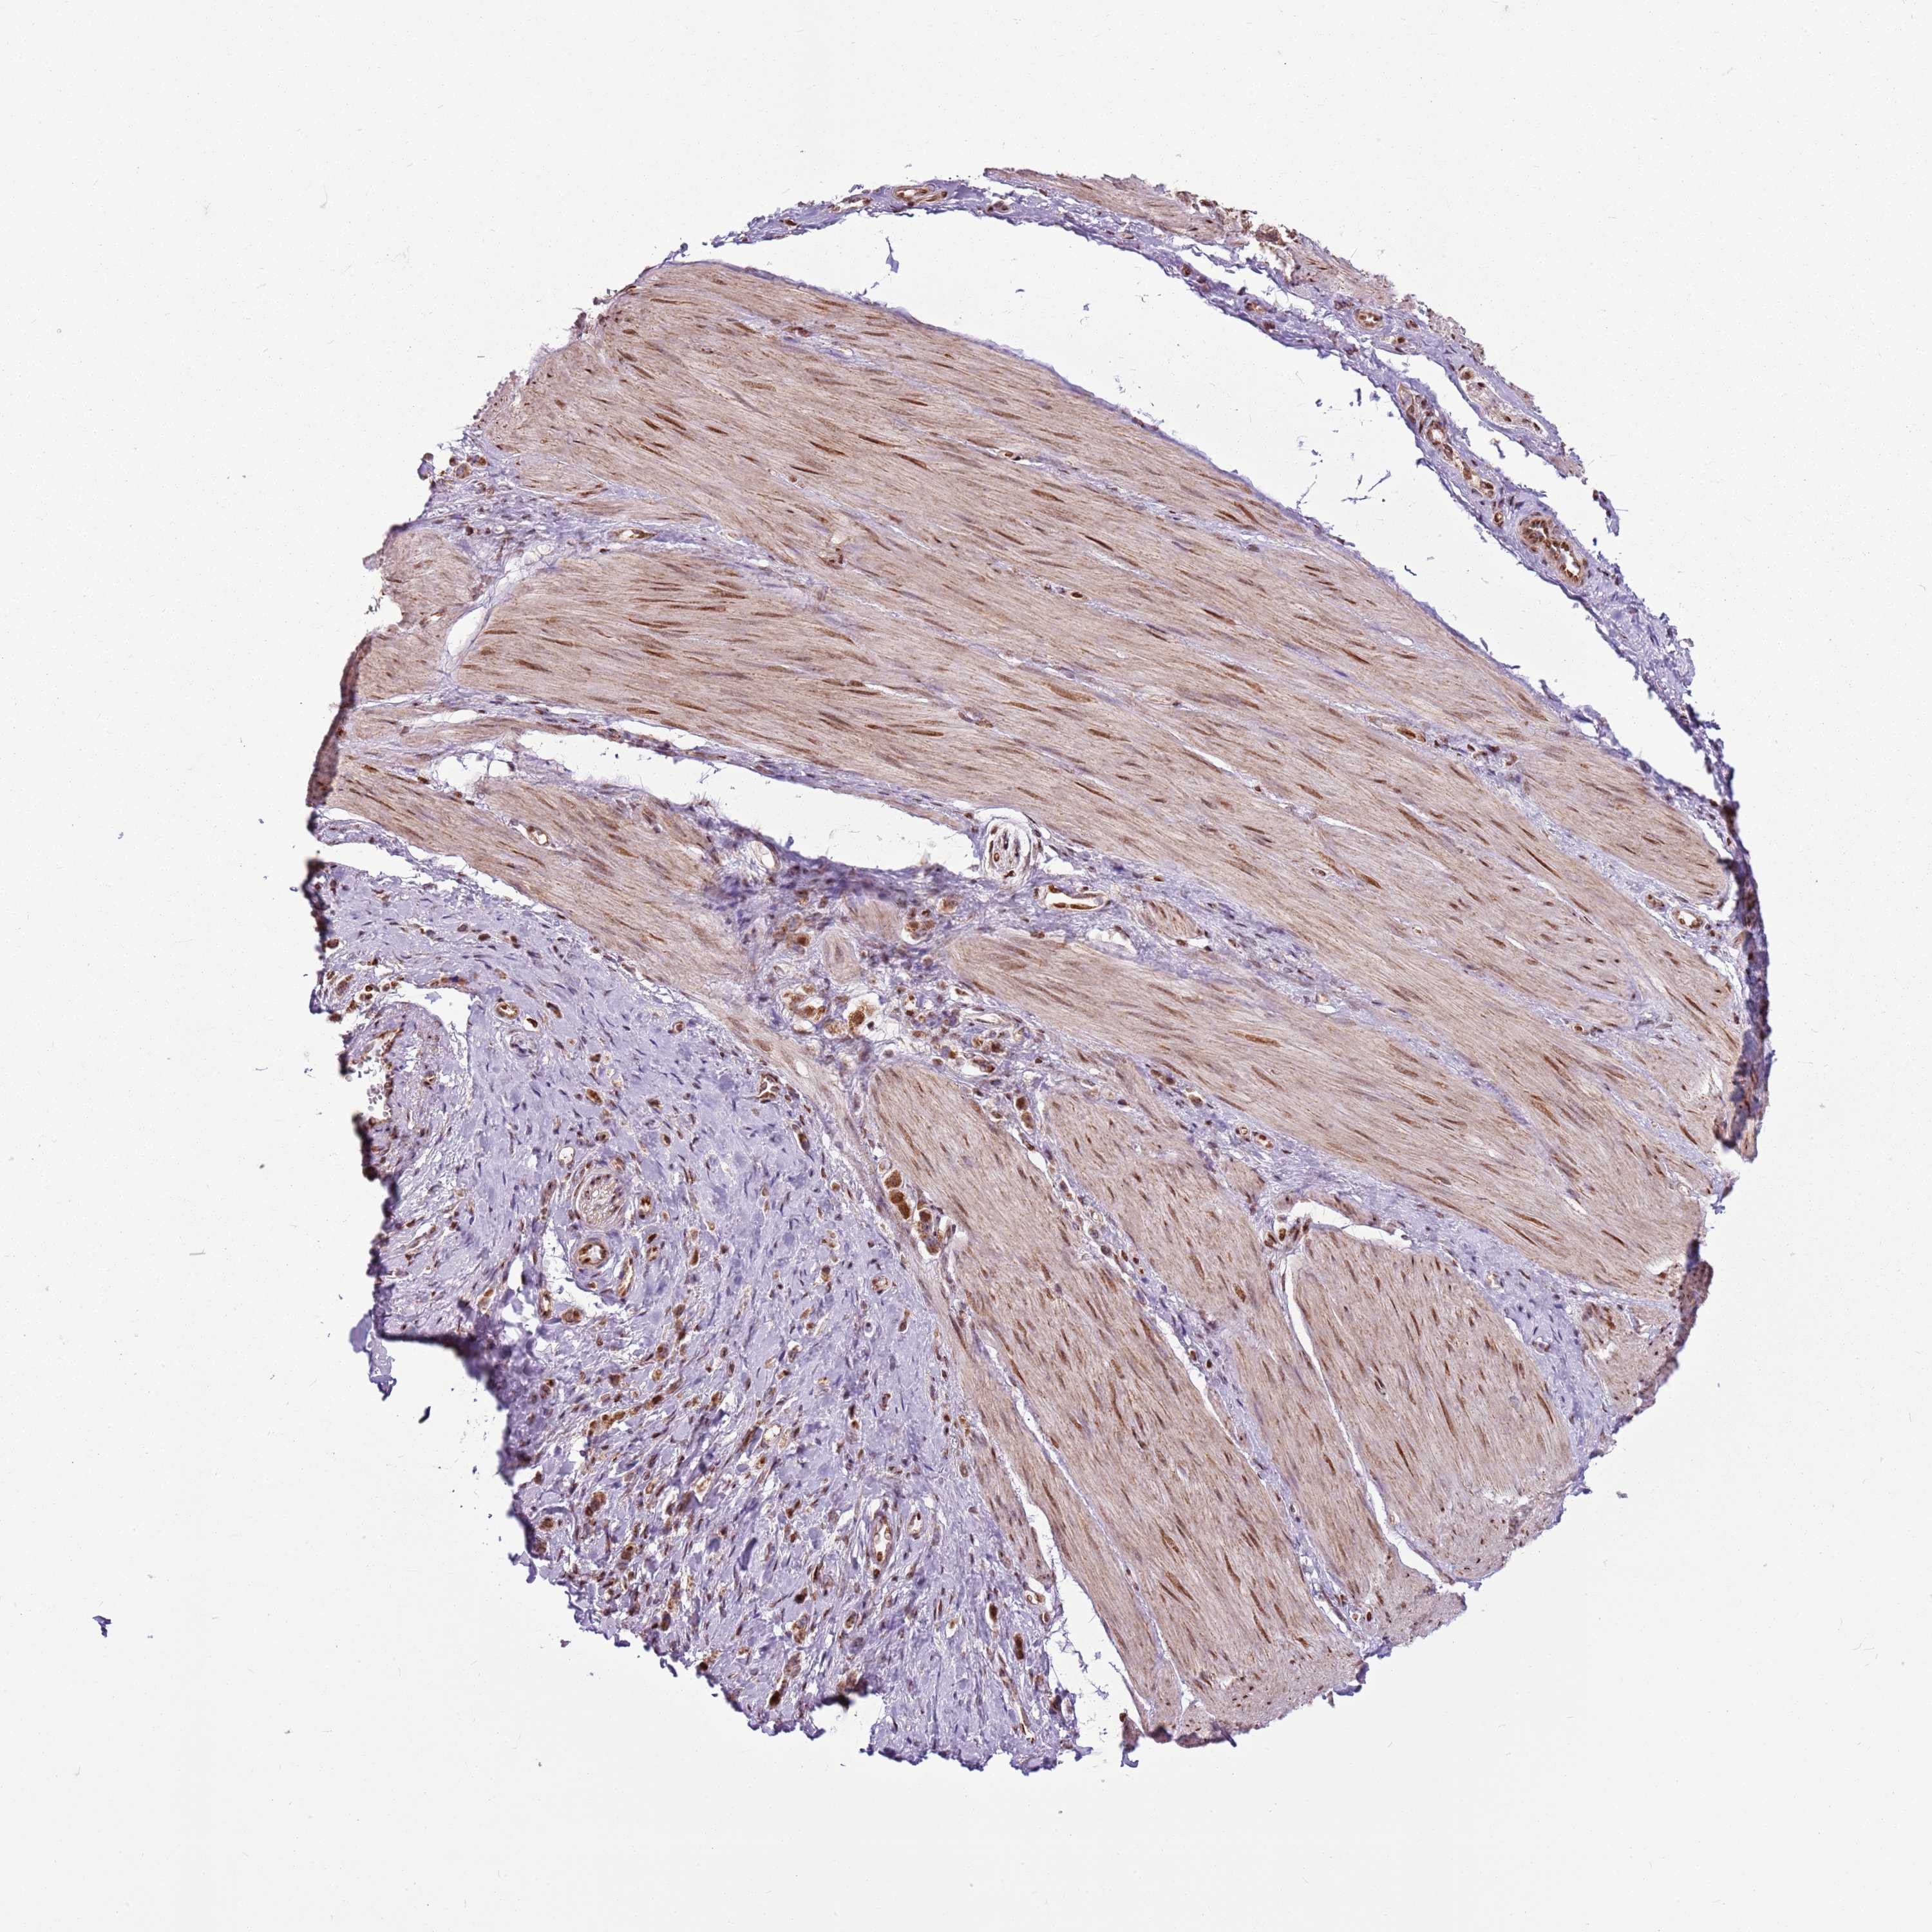

STOMACH CANCER - Protein expressioni

A mouse-over function shows sample information and annotation data. Click on an image to view it in a full screen mode. Samples can be filtered based on level of antibody staining by selecting one or several of the following categories: high, medium, low and not detected. The assay and annotation is described here.

Note that samples used for immunohistochemistry by the Human Protein Atlas do not correspond to samples in the TCGA dataset.

Antibody stainingi

Antibody staining in the annotated cell types in the current human tissue is reported as not detected, low, medium, or high, based on conventional immunohistochemistry profiling in selected tissues. This score is based on the combination of the staining intensity and fraction of stained cells.

Each image is clickable and will lead to virtual microscopy that enables deeper exploration of all samples and also displays staining intensity scores, fraction scores and subcellular localization as well as patient and tissue information for each sample.

Antibody HPA022979

Staining

High

Medium

Low

Not detected

Intensity

Strong

Moderate

Weak

Negative

Quantity

>75%

75%-25%

<25%

None

Location

Nuclear

Cytoplasmic/membranous

Cytoplasmic/membranous,nuclear

Adenocarcinoma, NOS